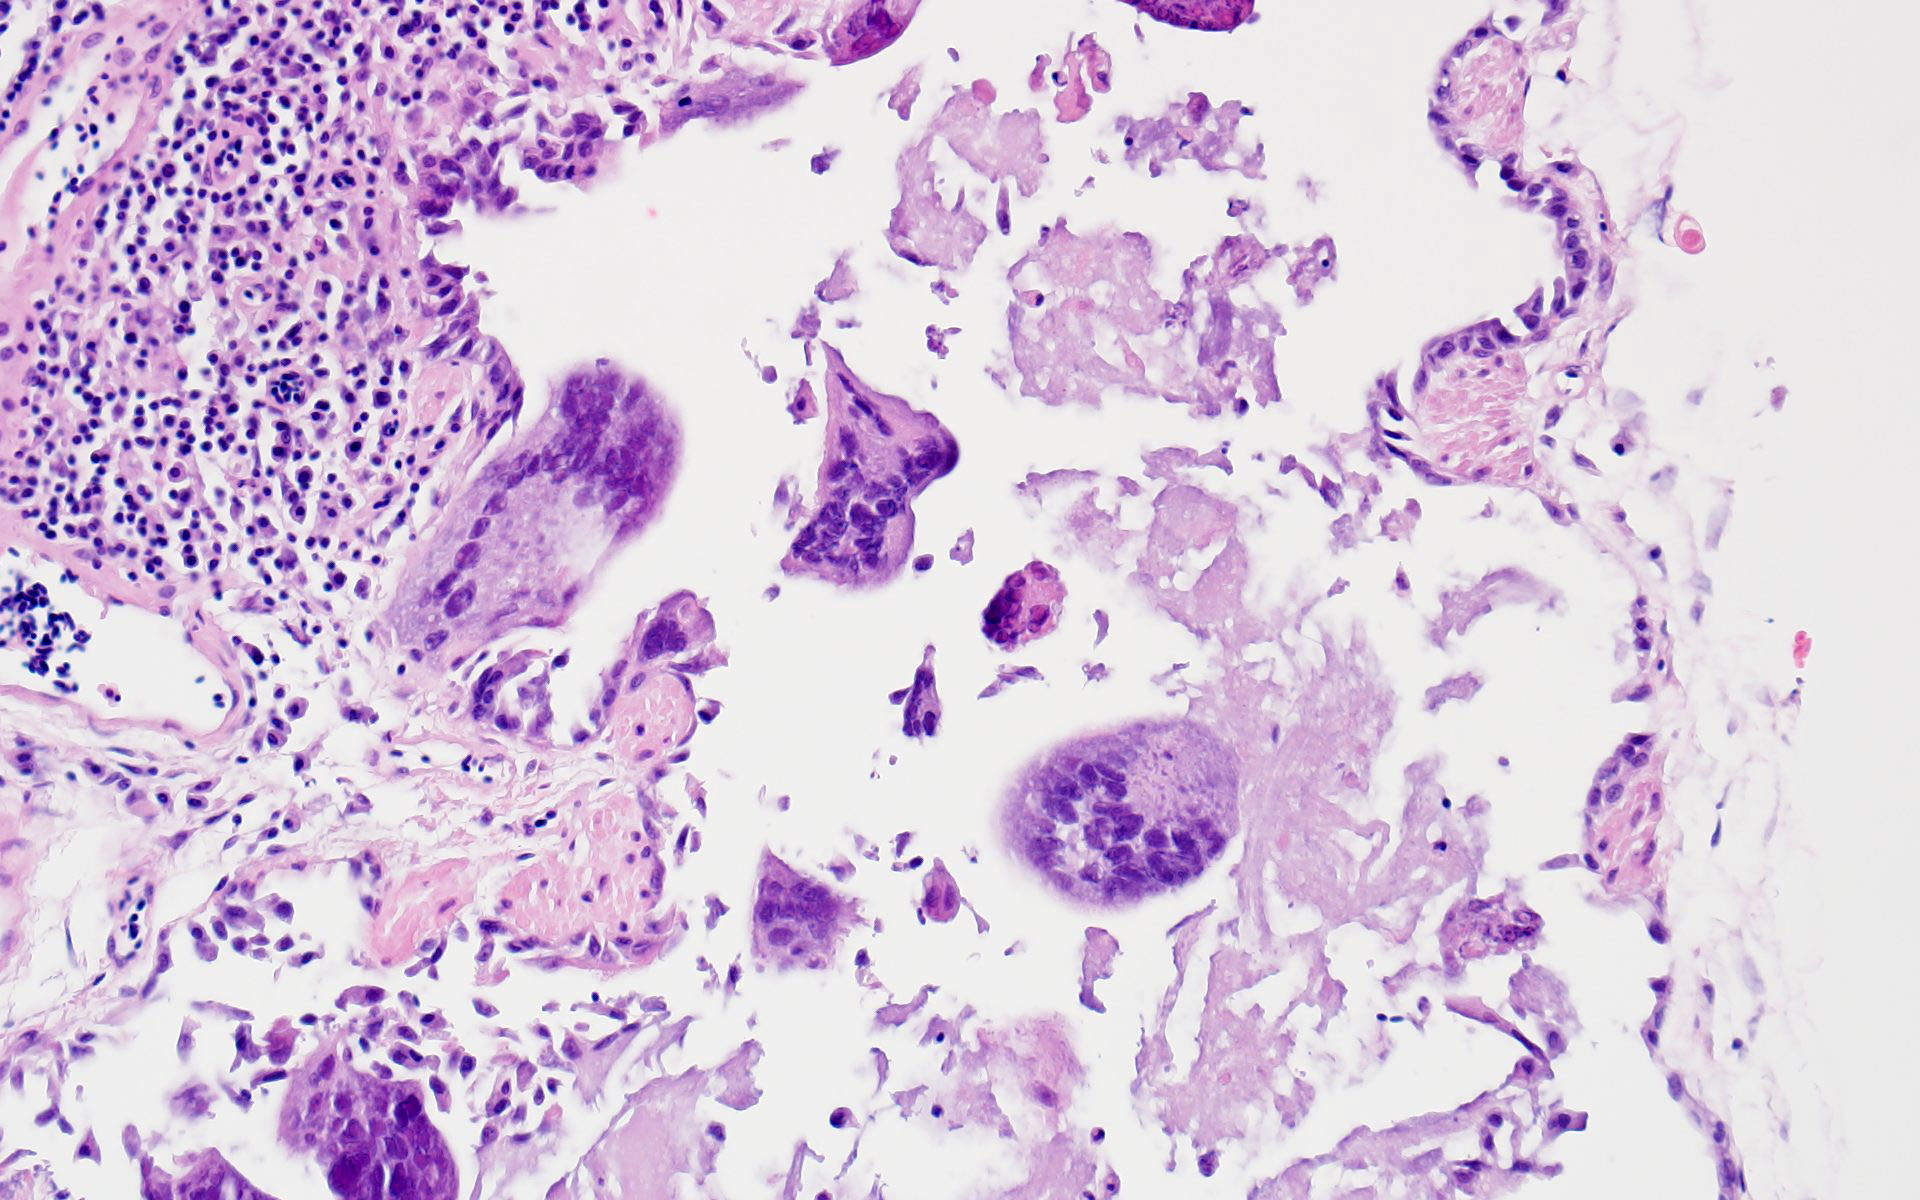

- Tubular reproductive tract, air sac, lung: Epithelial necrosis, acute, multifocal, moderate, with intranuclear viral inclusions and numerous syncytia.

The JPC’s own Dr. Elise LaDouceur moder-ated this year’s avian-focused seventeenth conference. This first case provided participants with a panoply/salmagundi/”dog’s breakfast” of tissues to sort through to achieve a diagnosis. The characteristic intranuclear viral inclusion bodies of herpesvirus were best seen in the air sac respiratory epithelium, which also rewarded conference-goers with some exceptional viral syncytia. Of the potential herpesviral culprits, psittacine al-phaherpesviruses (PsAHV) 1, 3, and 5 have been reported in psittacine species, including Indian ringneck parakeets, and PsAHV-5 was isolated by the contributor in this case. The contributor provided some beautiful electron microscopy (EM) photos from this bird that demonstrated intranuclear herpesviral virions, with some virions budding from the nuclear envelope to become enveloped themselves, and others hanging around the rough endo-plasmic reticulum (RER) to acquire additional proteins. The JPC is grateful to the contributor for providing these excellent educational images!

In addition to the respiratory epithelium, a tubular structure adjacent to the ovary was also affected by PsAHV-5 (i.e., had syncytia and epithelial necrosis). The smooth muscle wall and cellularity of this structure is consistent with either oviduct or remnant Wolffian duct. This suggests that PsAHV-5 may have a broader epitheliotropism beyond respiratory epithelium.